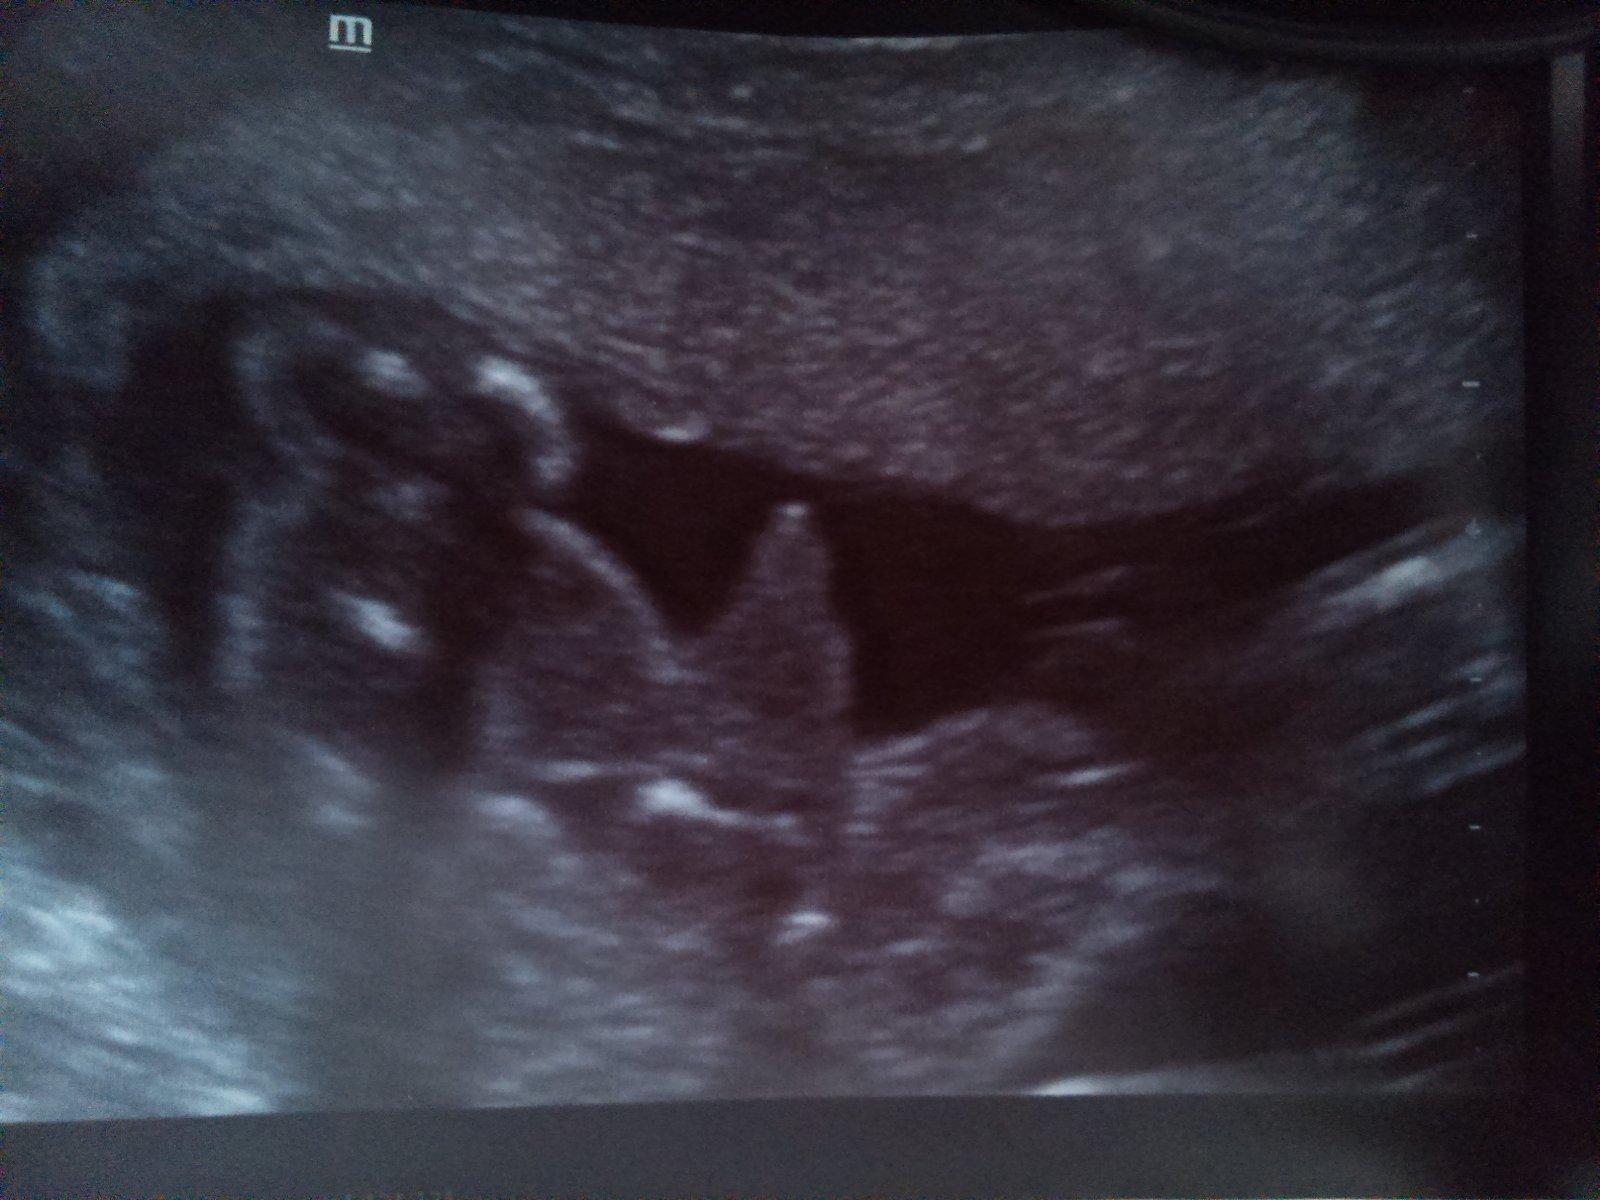

Holka nebo kluk?

@janulinka03 podle me t vypada jak prekrizene nohy takze tezko rict 😀

@janulinka03 je to docela podobný..ale nám to tam nějak víc vyčnívá... tak tohle by spíš mohla bý holčička 😀 ??

jasnen no vidis a me rekla doktorka spis chlapecek 🙂 my uz jednoho klucinu mame tak sem chtela holcicku, ale i tak sem moc rada pokud to tak bude! A ja vidim spis chlapecka u tebe, ale urcite to bude naopak 😀 a holcicka 🙂